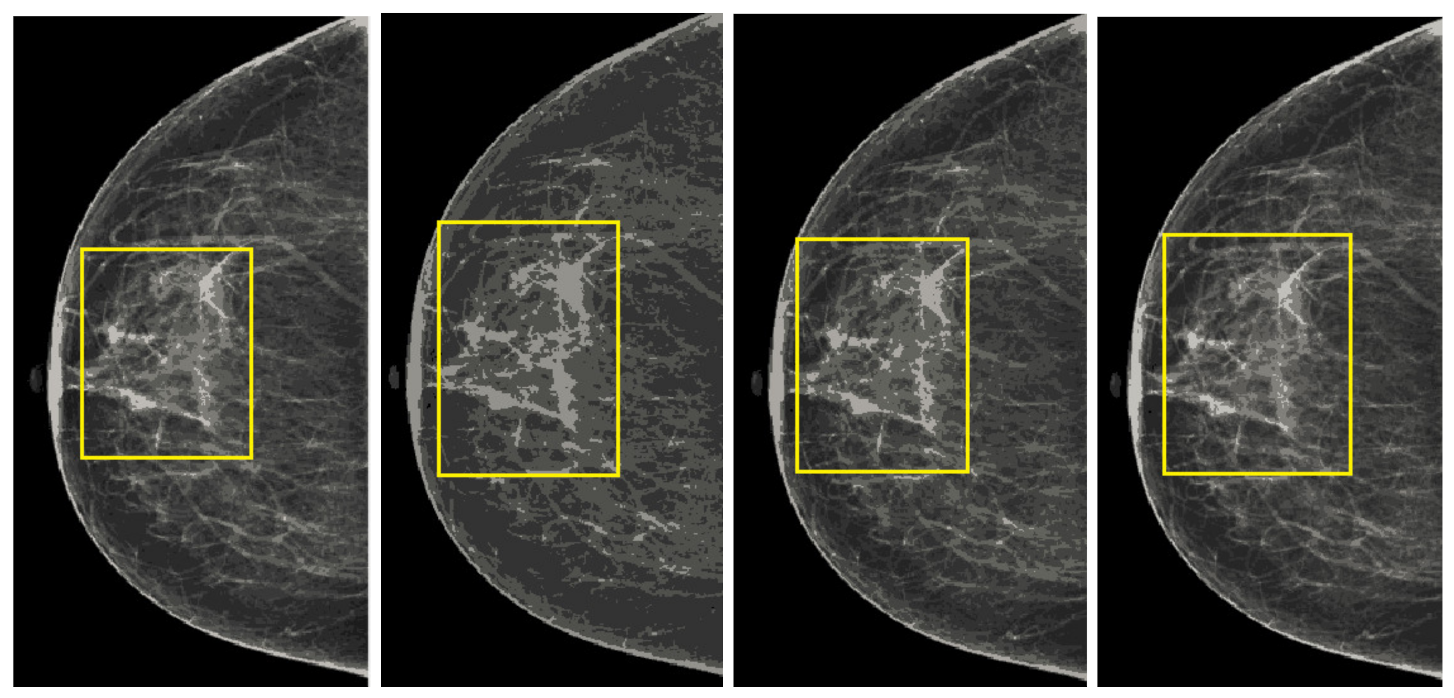

Mammographic image coherency contains two steps, the first step is based on the second-order Gaussian Laplacian (LoG) to normalize the set of mammography images as the output is shown in Figure 6. Although some regions, especially the regions containing a breast mass, the pixels are low intensities. These low pixels areas are not observed correctly, making it difficult to segment the cancerous area. We used oriented diffusion filtering as a second step to obtain a well-normalized image.

Figure 6.

Mammogram coherent images. (a) Second order Laplacian of Gaussian output image and (b) anisotropic oriented diffusion filter image.

The more coherent images lead to more precise segmentation of the cancerous region from the mammography images. We apply the oriented diffusion filter [46] for coherent areas of low contrast region, as it is a suitable filtering method for normalized regions with low contrast. The oriented diffusion filter requires the recomputed orientation data of the image in advance, and this orientation data is called the orientation field (OF). The orientation field makes the diffusion tensor with the flow of the pixels of the image. The primary motivation for using an anisotropic diffusion procedure is based on the tilt angle of the best ellipse. It is achieved through the Second Order Gaussian detector, which gives the right direction for the low contrast region. The diffusion procedure is defined as follows:

The diffusion process is an iterative algorithm that processes the pixels from the initial mammography images to develop a smoother structure with each step [47]. The fine structure is achieved with a normalized image; there should be an appropriate stop criterion to get a fine structure. The stopping criterion is introduced in recent research works. The stop iteration process of the stop criterion is based on the rate of change of the spatial entropy value of the image relative to the number of iterations. The Figure 6a shows the output of the anisotropic oriented diffusion filter, and the output of the second-order Gaussian filter is also shown in the Figure 6b. It observed that this anisotropic oriented diffusion filter gives more coherence to the images in particular area, especially the area of the breast concerning the background compared to the Gaussian second order filter.